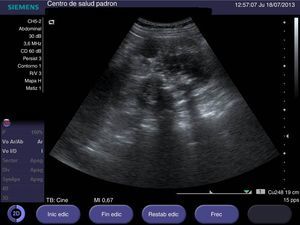

Mujer de 61 años de edad sin antecedentes de interés, que consulta en atención primaria por hematuria objetivable de 15 días de evolución. Presenta cuadro catarral en los días anteriores, sin otros datos de interés. En la exploración física se aprecia masa palpable en hipocondrio derecho. Se realiza ecografía en su centro de salud obteniéndose las siguientes imágenes (figs. 1 y 2).

La unión de hematuria y masa palpable en hipocondrio derecho nos orienta hacia un proceso maligno como primera posibilidad. En la ecografía realizada en atención primaria observamos un riñón derecho con discreto aumento de tamaño (12,9cm de longitud en el riñón derecho versus 9,5cm en el riñón izquierdo, en una mujer de 155cm de estatura) y parénquima renal muy desestructurado (es difícil ver en este caso la estructura ecográfica típica renal: corteza, médula y seno renal). También destaca la presencia de abundantes imágenes hiperecoicas con sombra posterior (sugestivo de calcificaciones groseras), sin que se observen imágenes de ectasia renal. El aumento de tamaño y la desestructuración de la arquitectura renal nos hacen pensar en enfermedad neoplásica. La presencia de las numerosas calcificaciones groseras (que no sugieren enfermedad litiásica) nos lleva a proponer una hipótesis diagnóstica muy infrecuente: carcinoma renal de tipo sarcomatoide.